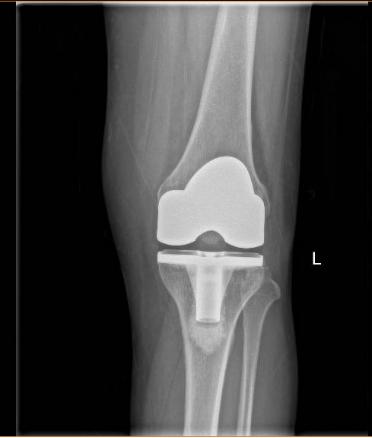

反复讨论制定了完善的膝关节置换手术计划和术后康复方案,刘宁主任向范阿姨介绍道:膝关节置换术就是将膝关节损坏的部分切除,换上新的活动关节,使膝关节稳固,受力平衡,从而消除疼痛,手术使用的材料是钛合金部件和高分子量聚乙烯垫片,跟人体相容性好,极少出现排斥反应。

术后第1天,范阿姨便能下地无痛行走,这让她感到十分惊讶和欣喜!术后第5天,范阿姨便顺利出院。